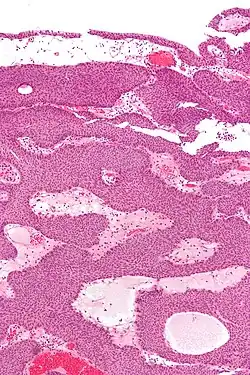

Histopathology representing an inverted papilloma of the urinary bladder that was cystoscopically resected. Hematoxylin and eosion stain. -